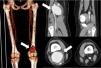

The findings of an ultrasound scan (Fig. 1) and a CT angiogram (Fig. 2) led to diagnosis of giant popliteal aneurysm. The echocardiogram and ophthalmological evaluation were normal. The patient was classified as high priority to underwent early surgical intervention (Fig. 3), consisting of reversed saphenous vein grafting.